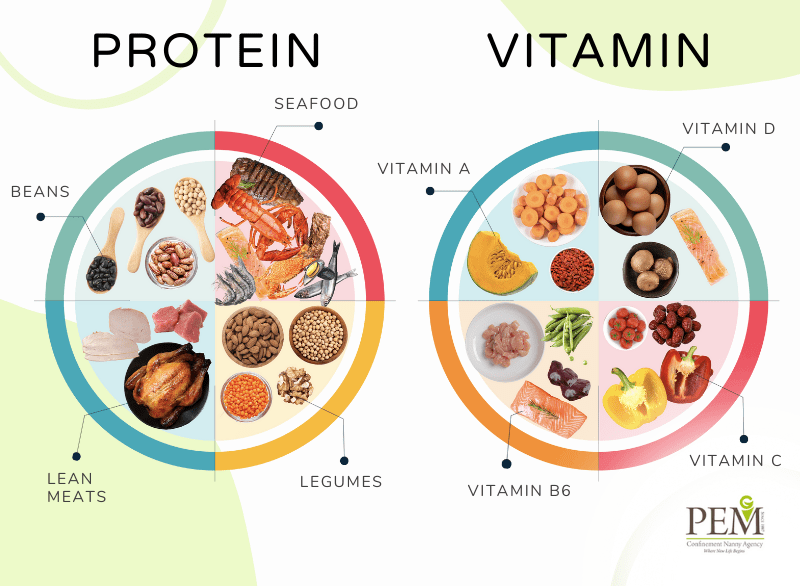

Best Foods For Mothers After Cesarean Section PEM Confinement

Best Foods For Mothers After Cesarean Section PEM Confinement

Foods You Can Eat After C Section Diet Plan For Cesarean Mother

Foods You Can Eat After C Section Diet Plan For Cesarean Mother